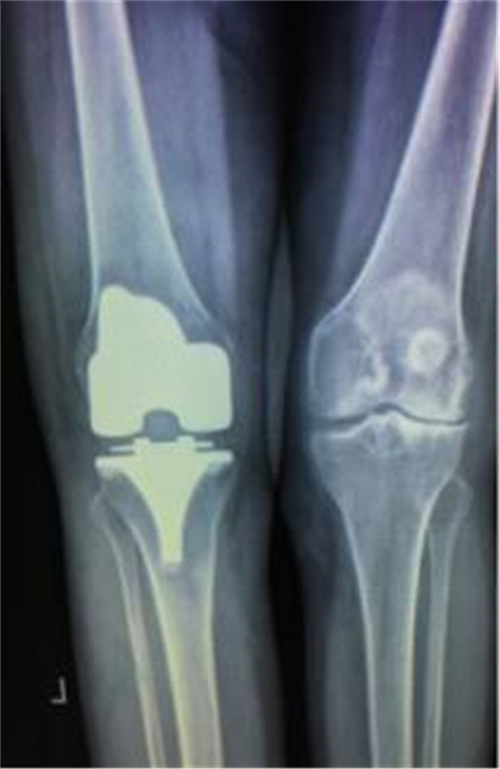

术前X线

术后X线

得知郴州市第四人民医院骨科掌握了这一手术技术,便前来就诊。谭主任接诊到该患者后,对其进行了详细的体格检查,发现其左膝关节僵直,屈伸活动不能,负重时膝关节疼痛明显加重,膝关节X线片提示膝关节退变严重,关节间隙明显变窄,并有游离体形成,诊断为左膝关节重度骨关节炎并关节僵直,有明确的膝关节置换手术指征。

经过与家属的耐心沟通,谭宜昌主任及其团队决定为谢某实施膝关节置换手术。8月25 日上午,谭主任及其团队历时90分钟,成功为患者实施了膝关节置换术。术后患者的膝关节畸形矫正,膝关节稳定性也已恢复,膝关节功能明显改善。出院时谢某脸上洋溢着满意的笑容,说非常感谢谭主任团队把折磨自己多年的疾病给治好了。